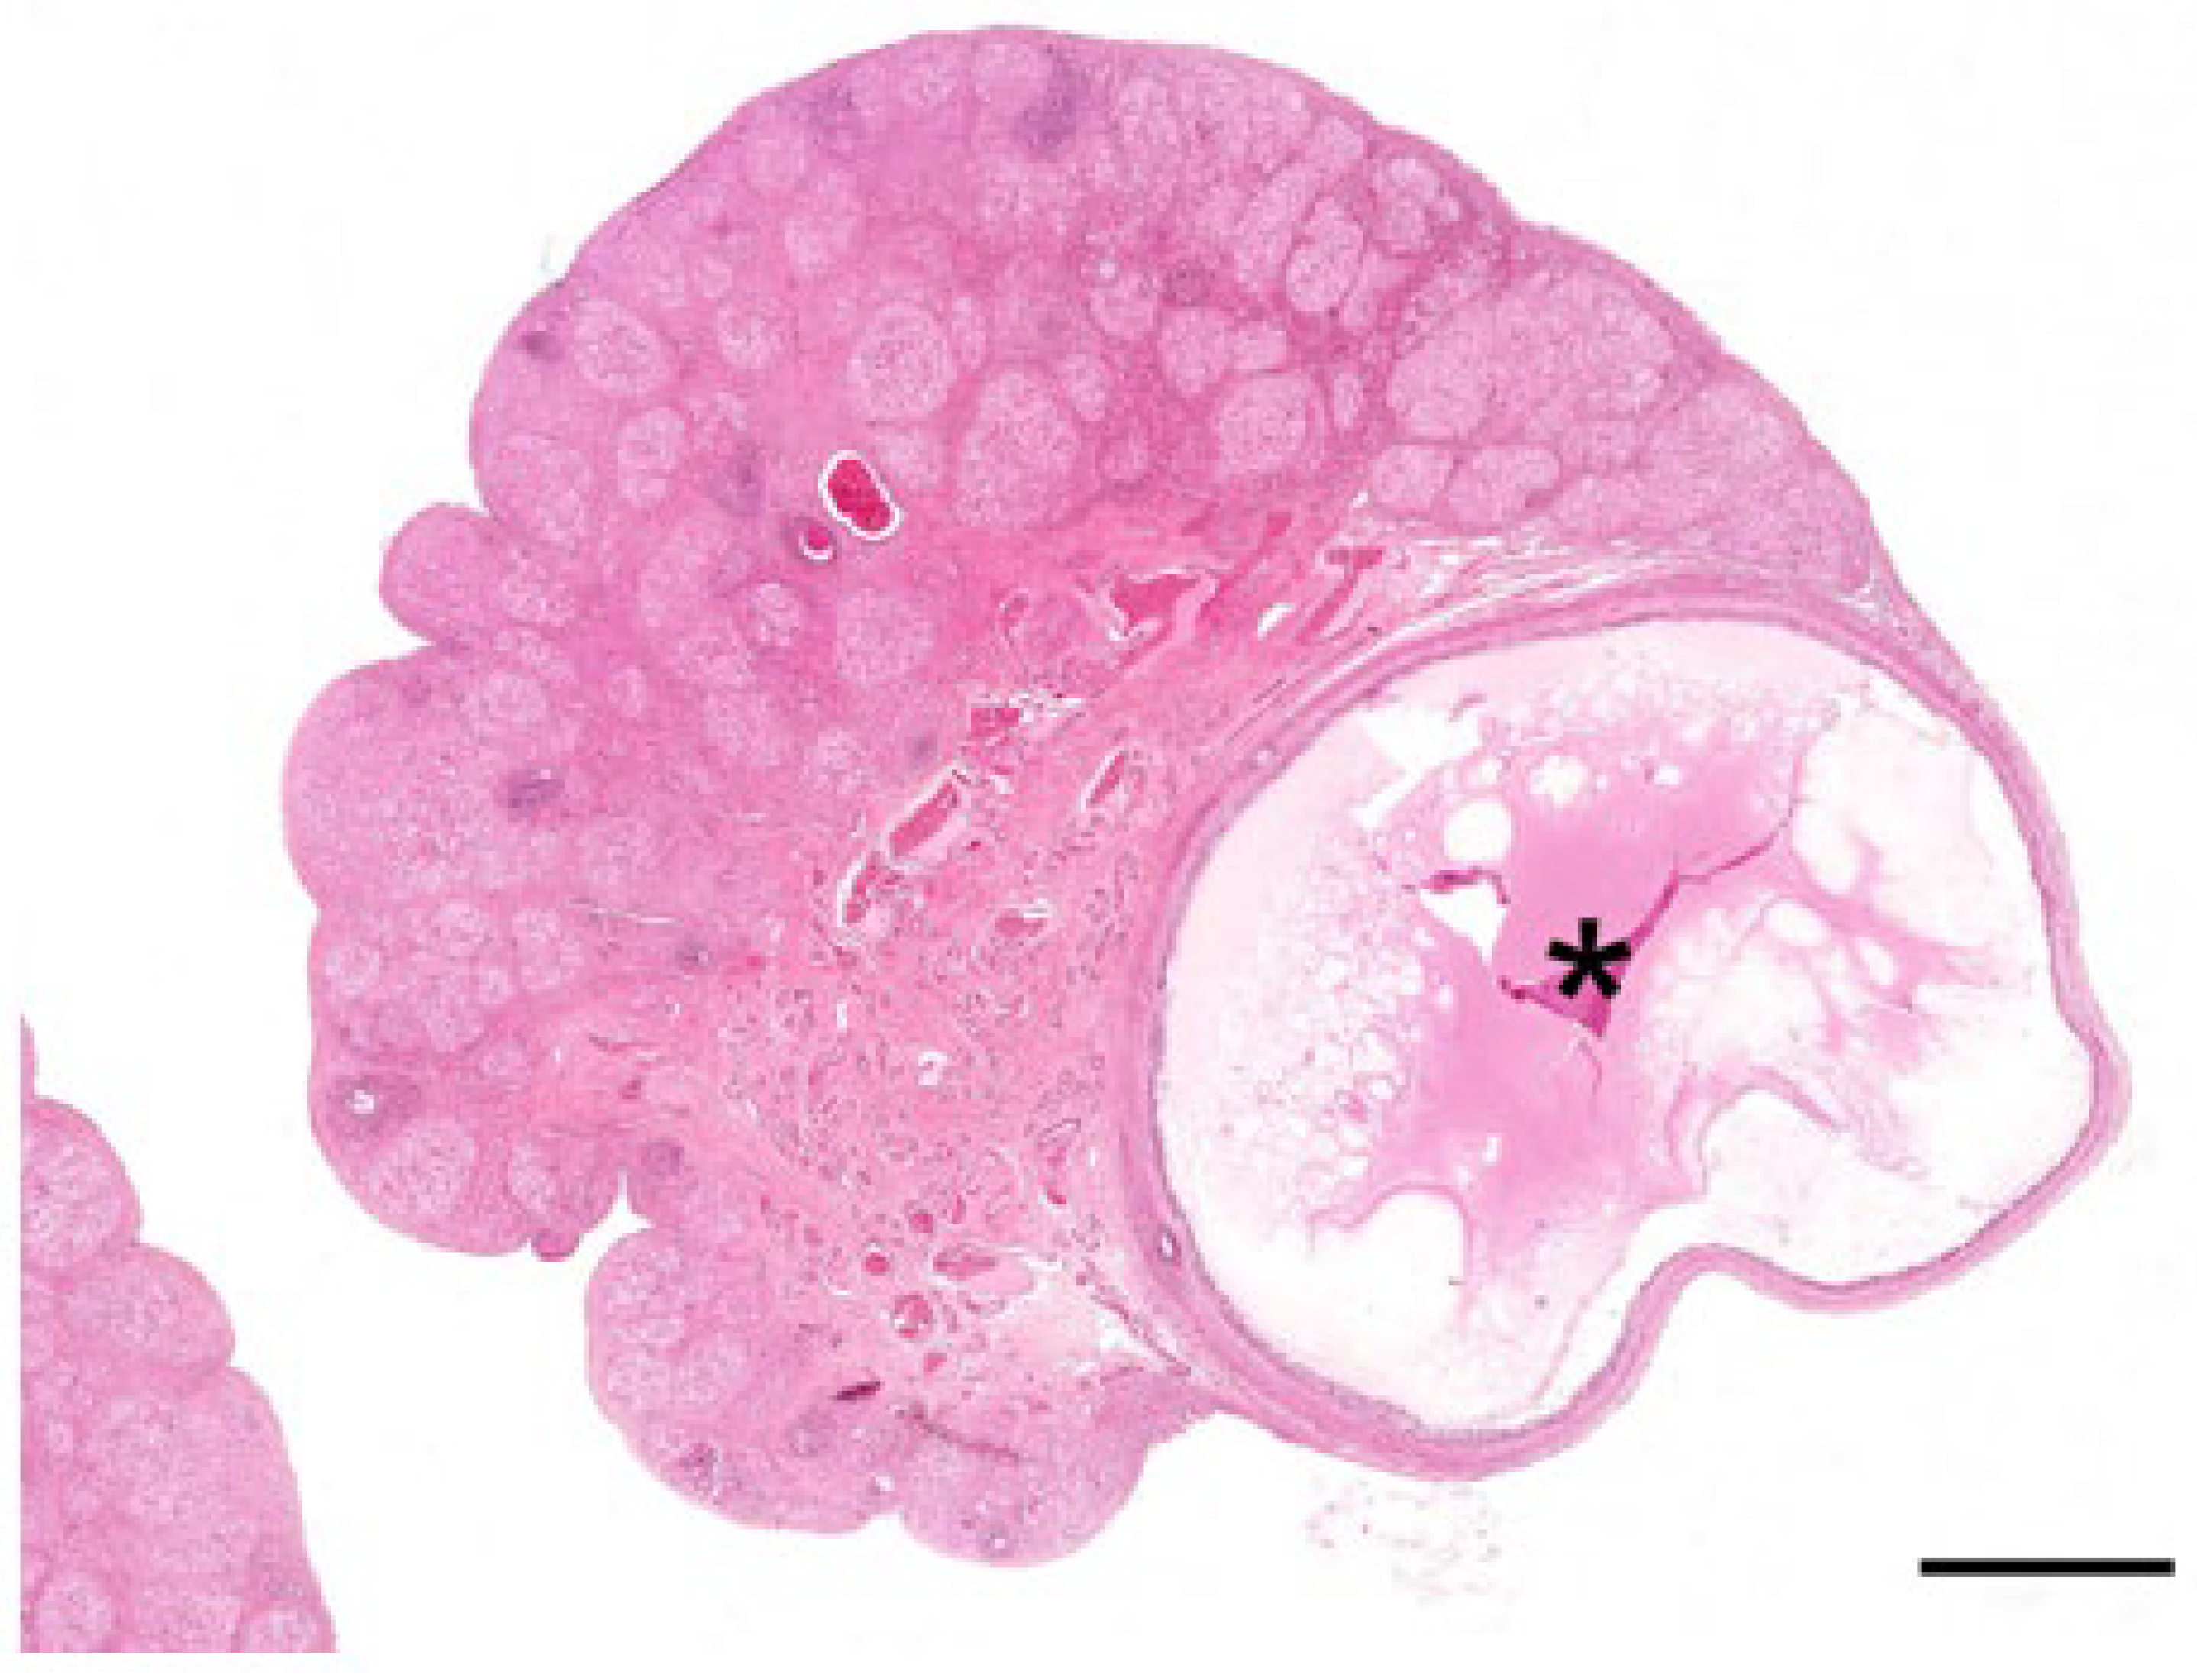

Figure 3.

Histological features of the koala’s ovary in the interestrous phase. (A) Outer cortical and inner medullary region of the ovary, converging into the hilus containing numerous blood vessels (asterisk). HE. Bar = 1 mm. (B) Primordial follicle with an oogonium surrounded by a single layer of flat follicular cells. HE. Bar = 20 µm. (C) Primary follicle with a central oocyte surrounded by a single layer of cuboidal follicular cells. HE. Bar = 20 µm. (D) Secondary follicle with columnar follicular cells and the appearance of the zona pellucida (arrow). HE. Bar = 20 µm. (E) Early stage of antrum formation (asterisk) with multiple layers of follicular cells. HE. Bar = 20 µm. (F) Graafian follicle with theca cells (arrow) and a single cavity containing follicular fluid (asterisk). HE. Bar = 100 µm.